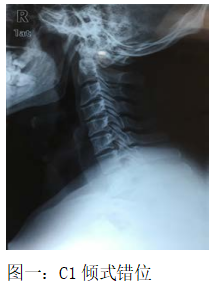

辅助检查:阅外院DR示:颈椎生理曲度变直;C1旋转式错位;C1倾式错位,C5~C6旋转式错位。(图一)

3、影像学:DR示:颈椎生理曲度变直;C1 旋转合并C1 倾式错位,C5 、C6 旋转式错位。结合三步定位诊断,可明确诊断为:1、颈源性高血压;2、混合型颈椎病。病因分型:关节功能紊乱型。